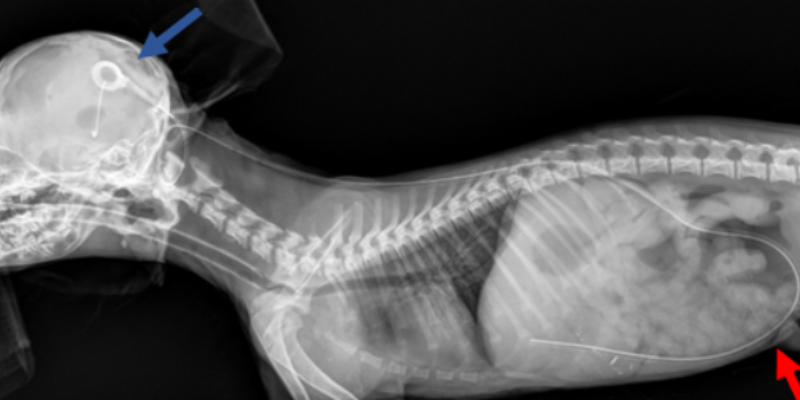

Pictured is a post-operative radiograph of a young dog with obstructive hydrocephalus that had a ventriculoperitoneal shunt placed. The blue arrow points to the shunt in the brain and the red one to the abdomen shunt, Animal Emergency & Referral Center of Minnesota

Pictured is a post-operative radiograph of a young dog with obstructive hydrocephalus that had a ventriculoperitoneal shunt placed. The blue arrow points to the shunt in the brain and the red one to the abdomen shunt.